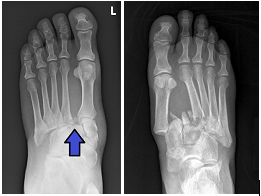

Diploma Orthopedics, Fellowship in Foot & Ankle Surgery from Vadodara, Chennai, Spain, U.K.

1st and only exclusive foot & Ankle surgeon of Saurashtra-Kutch region. Practicing orthopedics since 2014 with dedicated practice of ankle and foot surgeon since 2021